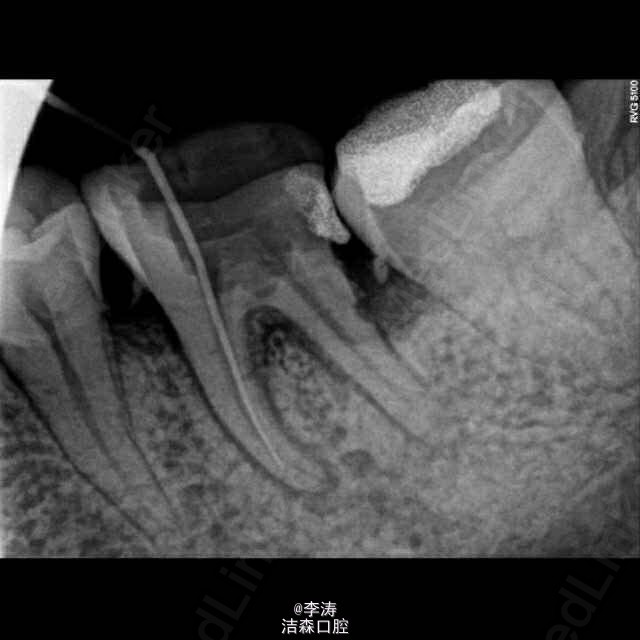

根管预备形成台阶1例

36牙根管治疗,近中根略弯曲,先疏通至15号,k3冠向下法预备,预备时形成台阶,然后怎么预弯都下不去! 太弯根管的还是应该使用手扩,特别是k3,弯曲根管尽量不用,容易形成台阶。另外预备过程中不能使用暴力!!